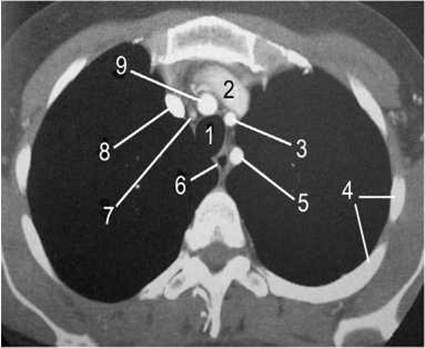

Мал. 103. Рентгенівська комп'ютерна томограма верхнього середостіння з внутрішньовенним контрастуванням у горизонтальній площині.

1 - трахея;

2 - ліва плечоголовна вена;

3 - ліва спільна сонна артерія;

4 - Ребра;

5 - ліва підключична артерія;

6 - стравохід;

7 - притрахейний лімфатичний вузол;

8 - права плечоголовна вена;

9 - плечоголовний стовбур.